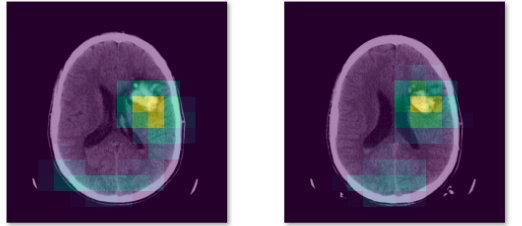

但是你需要改一改,怎么改呢 ? 我举个栗子:你可以做疾病分类,网上有很多的开源数据集,判断一张图片是猫还是狗和判断一张图片有没有病本质上是一样的。

如果你想搞一些花里胡哨的东西,可以借助注意力机制把病灶找出来,最终的效果就是:输入一张医疗图片,会输出这张图片患病概率,而且把这张图片上的病灶高亮出来。

对于一个本科毕业设计来说,我觉得做到这种程度足够了,如果你看不懂我刚刚说的技术名词,把我刚刚推荐的吴恩达深度学习教程看完,你就能明白了。